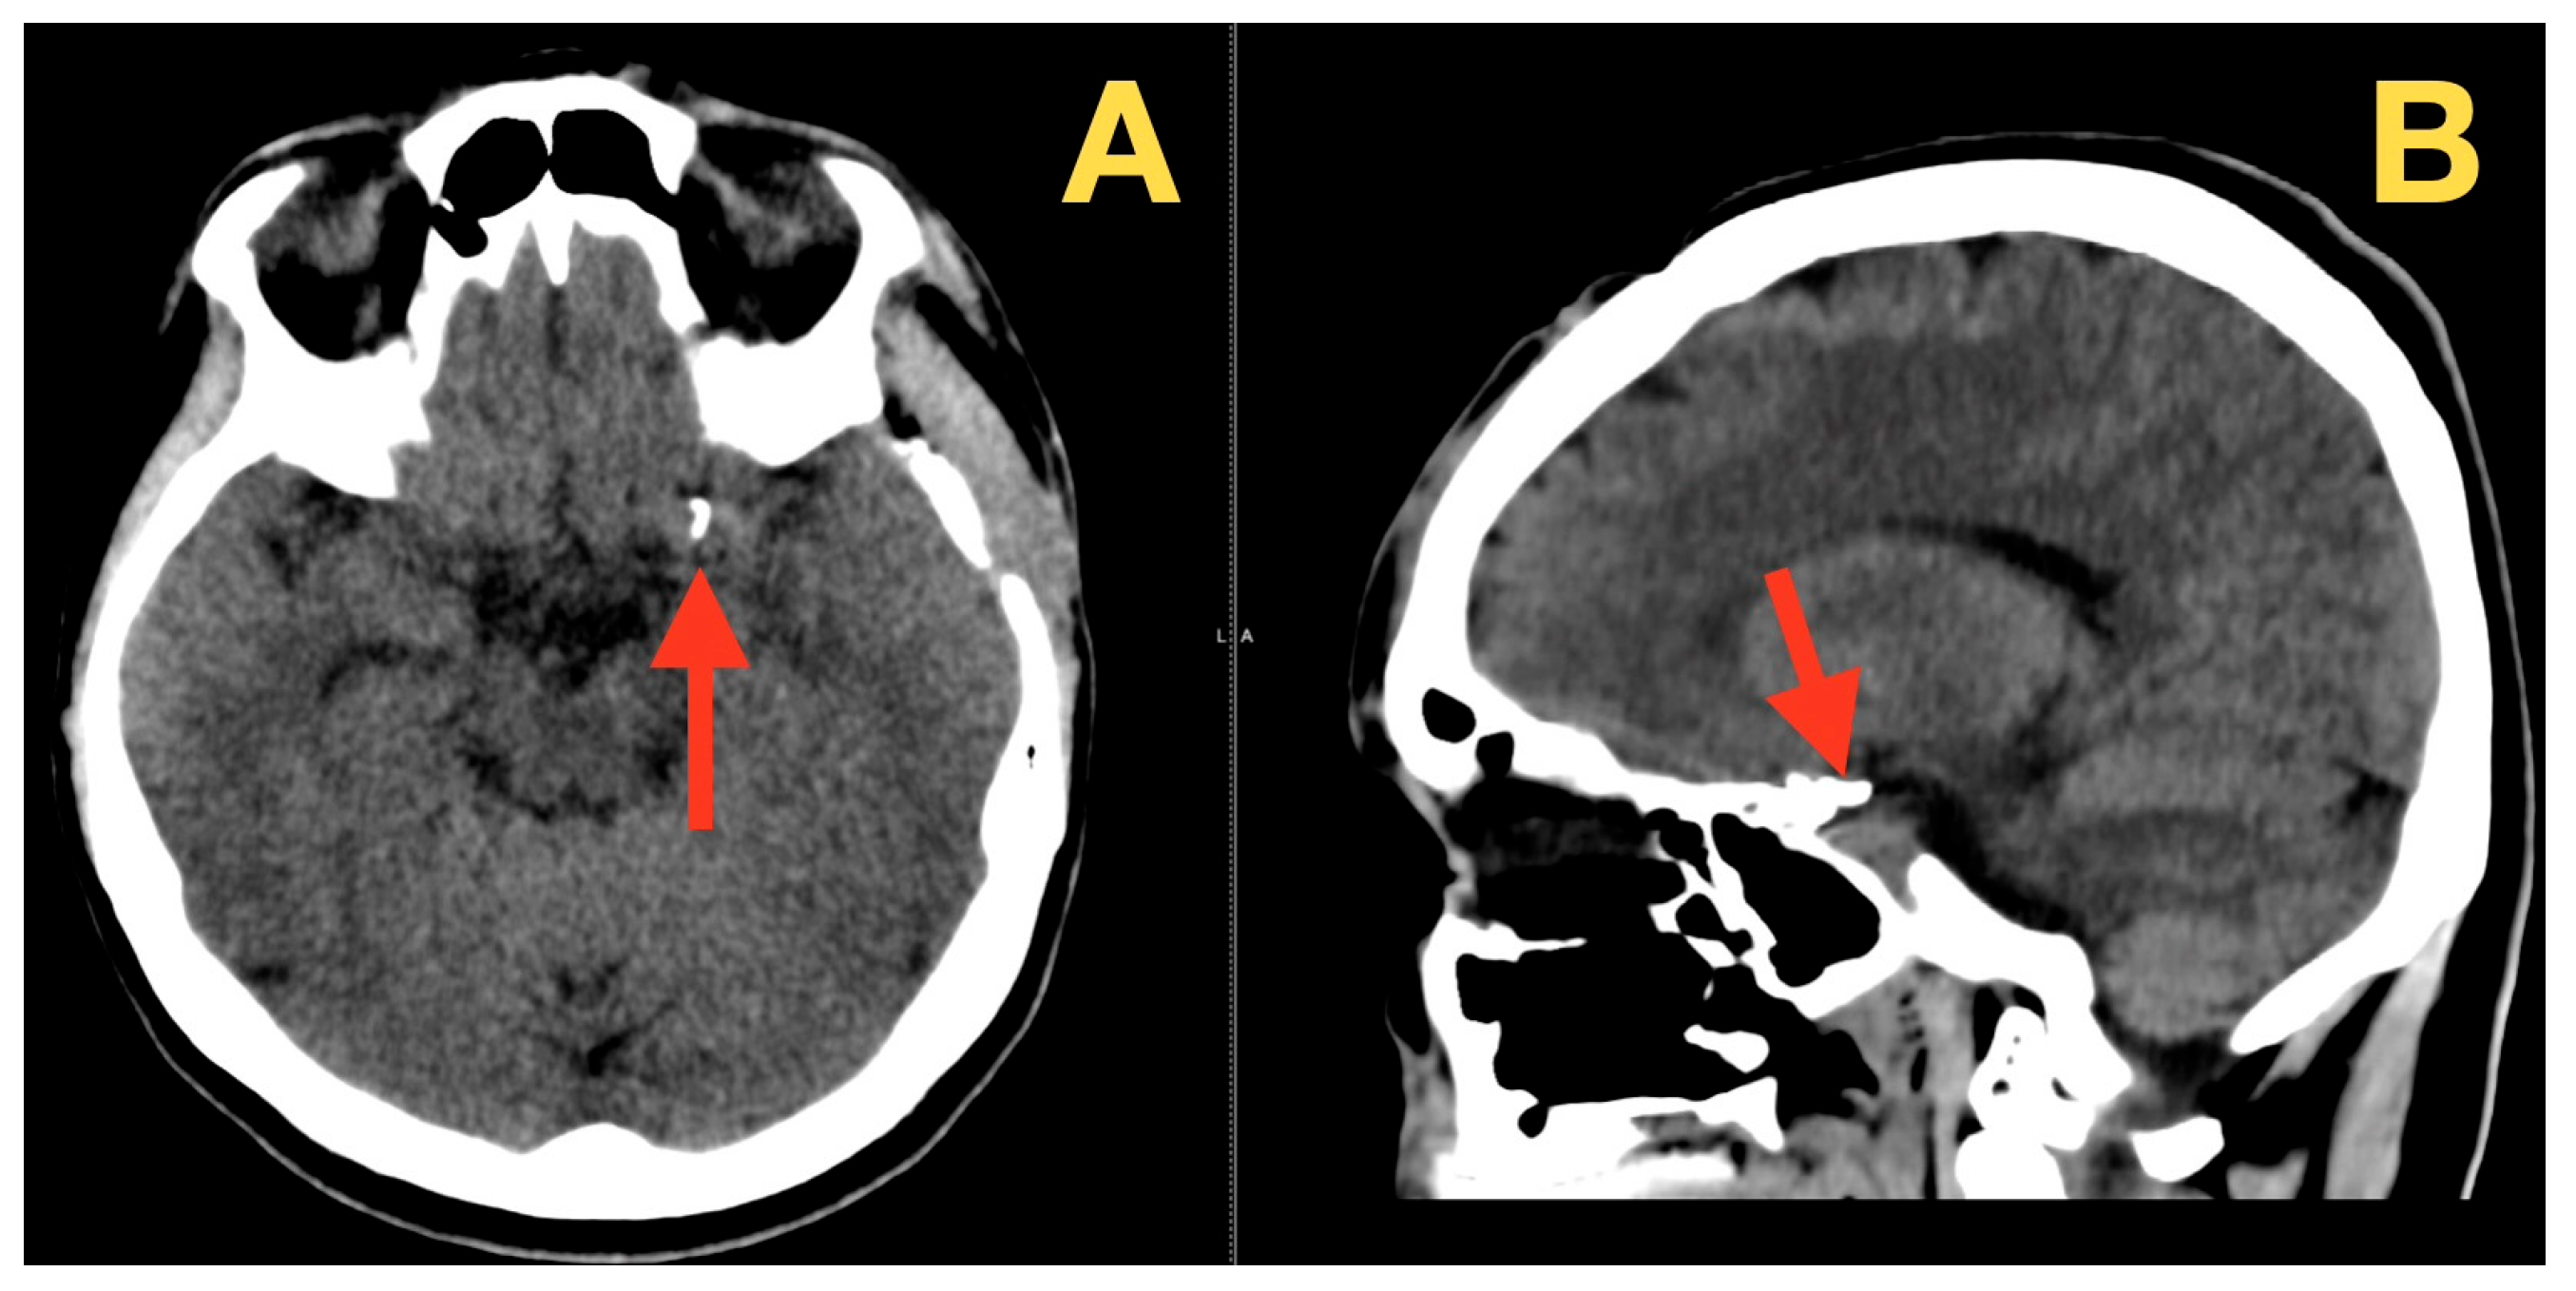

A Ruptured Tri-Lobulated ICA–PCom Aneurysm Presenting with Preserved Neurological Function: Case Report and Clinical–Anatomical Analysis

2. Case Presentation